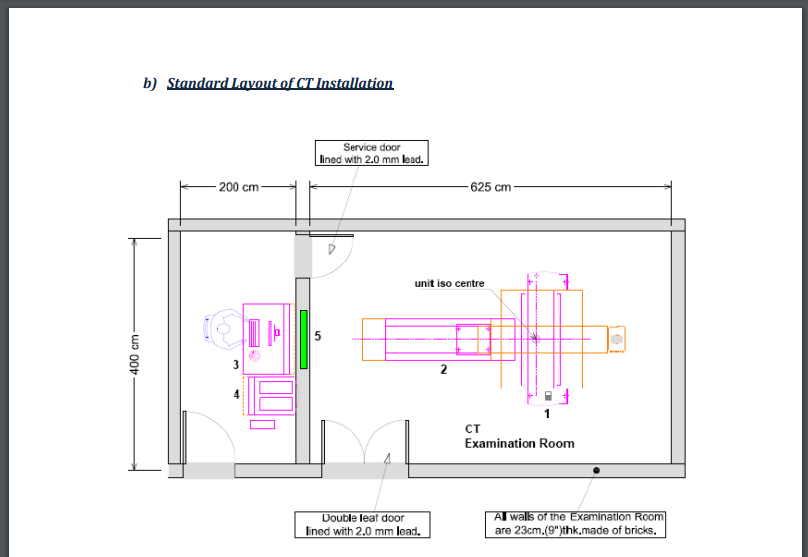

wallpaperaccess.comCt Scan Room Floor Plan - Floorplans.click

wallpaperaccess.comCt Scan Room Floor Plan - Floorplans.click

www.vecteezy.comCT Scan Room Size: What Do You Need To Know? - CTMRIHUB

www.vecteezy.comCT Scan Room Size: What Do You Need To Know? - CTMRIHUB